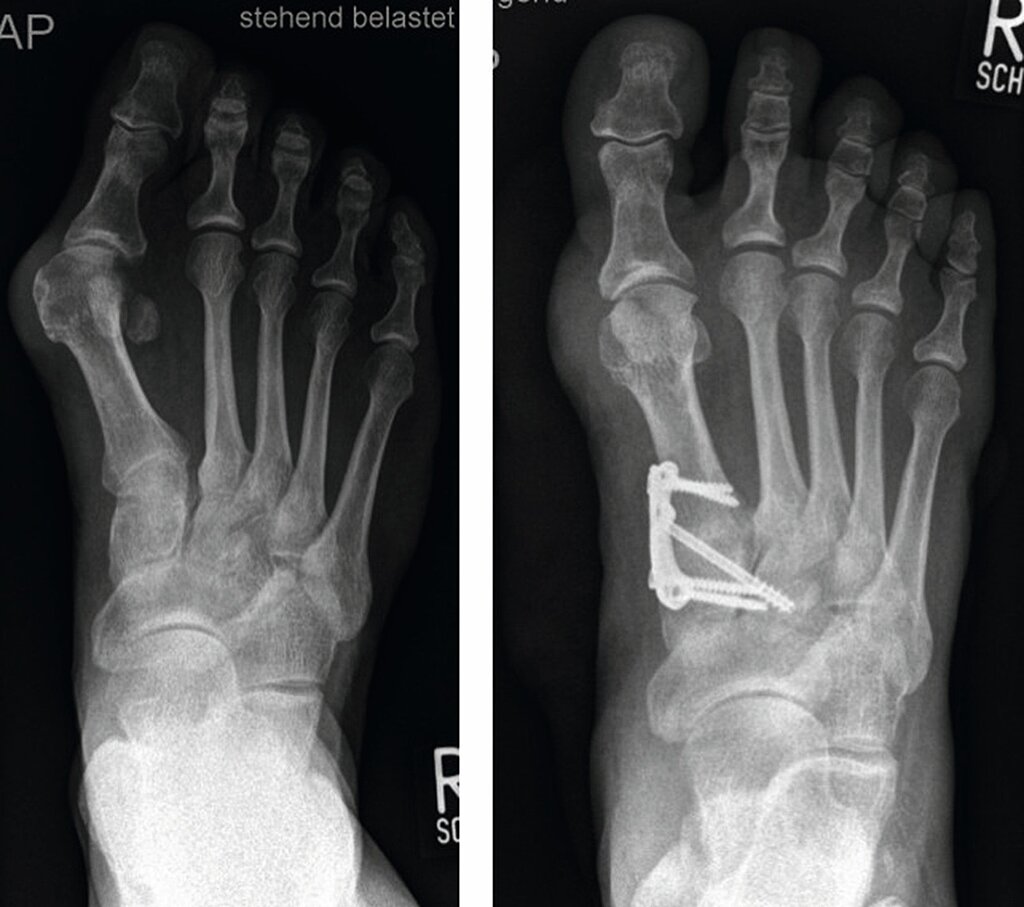

Indikation: Die Lapidusarthrodese wird beim schwerem Hallux valgus mit Intermetatarsalwinkeln > 18° und Hallux valgus Winkel meist > 40° und/oder instabilem Tarsometatarsal-1-Gelenk (TMT) und dadurch ausgelöstem Absinken des medialen Längsgewölbes durchgeführt.

OP-Technik (Abb. 7a, b): Nach mediodorsalem oder medialen Hautschnitt erfolgt Darstellung des Großzehengrundgelenkes und sparsame Abtragung der Pseudoexostose. Danach Präparation des TMT-Gelenkes unter Schonung des Ansatzes des M. tibialis anterior.

Dann wird das TMT-1-Gelenk entknorpelt oder im os cuneiforme 1 eine nach lateral (außen) offene Keilosteotomie (Knochendurchtrennung in Korrekturstellung) zur Korrektur des Intermetatarsalwinkels durchgeführt. Nach mehrfachem Penetrieren des Knochens erfolgt die temporäre Fixation mittels K-Drähten. Nach Röntgenbildwandler Kontrolle erfolgt die Osteosynthese mit winkelstabiler medialer, dorsomedialer oder plantarer Platte und meist zusätzlicher Zugschraube (Abb. 8). Der Abrollvorgang wird durch eine TMT-Versteifung nicht beeinträchtigt. Man sieht aktuell eine Tendenz unter Fußchirurgen, die schwere Hallux valgus-Deformität mittels dieser Technik zu versorgen.

Bei der Lapidusarthrodese kann neben lateralen release eine Korrektur des Gelenkwinkels bei pathologischem PASA-Winkel am Großzehengrundgelenkkopf ebenso wie eine Akin-Osteotomie notwendig werden. Wichtig ist das Erreichen einer achsgerechten Korrektur (Abb. 9a, b).